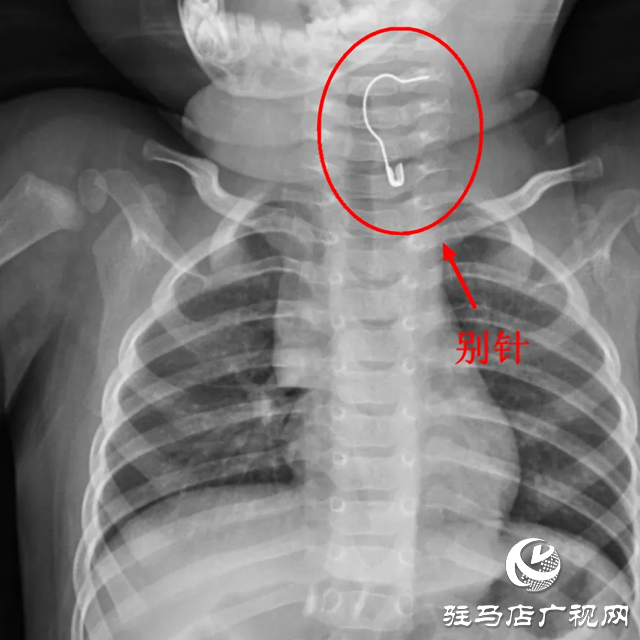

對(duì)于家里有小寶寶的家長(zhǎng)來(lái)說(shuō),最頭疼的事莫過(guò)于寶寶不管抓到什么東西,都喜歡往嘴里塞。十個(gè)月大的笑笑,在家玩耍時(shí),不小心吞下一枚別針,家長(zhǎng)趕緊送往當(dāng)?shù)蒯t(yī)院,但因異物特殊,笑笑連夜轉(zhuǎn)入駐馬店市中心醫(yī)院婦女兒童醫(yī)院,兒內(nèi)二科值班醫(yī)生史笑敏了解情況后,立即為笑笑安排X線(xiàn)檢查,發(fā)現(xiàn)金屬別針卡在笑笑的頸部食管入口。

別針處于張開(kāi)狀態(tài),尖端外露,危險(xiǎn)性不言而喻。史笑敏考慮到別針尖端非常尖銳,若刺穿食管,可能會(huì)出現(xiàn)食管穿孔;刺入血管,容易引起大出血;刺傷神經(jīng),可能會(huì)出現(xiàn)麻木、癱瘓等情況。在與笑笑父母充分溝通后,史笑敏立即聯(lián)系麻醉醫(yī)師和內(nèi)鏡中心護(hù)士為笑笑進(jìn)行急診手術(shù)。術(shù)中,內(nèi)鏡到達(dá)食管處,發(fā)現(xiàn)別針張開(kāi)的尖腳已經(jīng)扎進(jìn)了食管